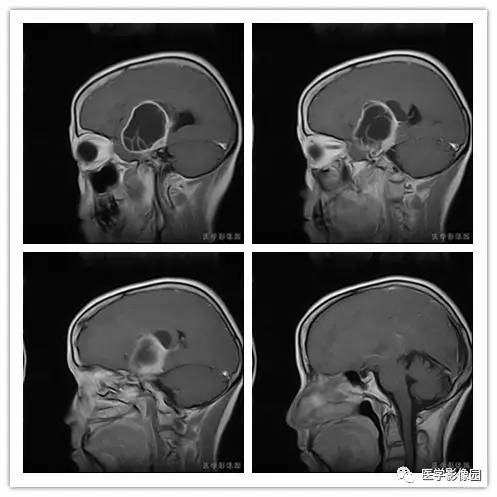

影像学表现:右侧颞叶深部区见一长T1、长T2囊样信号,成明显环形强化、未见明确结节影,没有FLAIR和DWI图,内见分隔,边界较清,周围水肿不明显,右侧脑室明显受压、颞角扩大,右侧脑沟明显变浅,脑中线结果向左偏移。

结果 血管外皮细胞瘤

1.肿瘤主要表现为等长T1 、等长T2 混杂信号影,偶可见短T1 或短T2 信号影,注药后,肿瘤增强明显但不均匀;

2.外形呈不规则分叶状;

3.半数以上的肿瘤与硬膜窄基底相连;

4.肿瘤内常可见血管流空影而见不到钙化影;

5.肿瘤附近骨质可见破坏而见不到增生硬化。